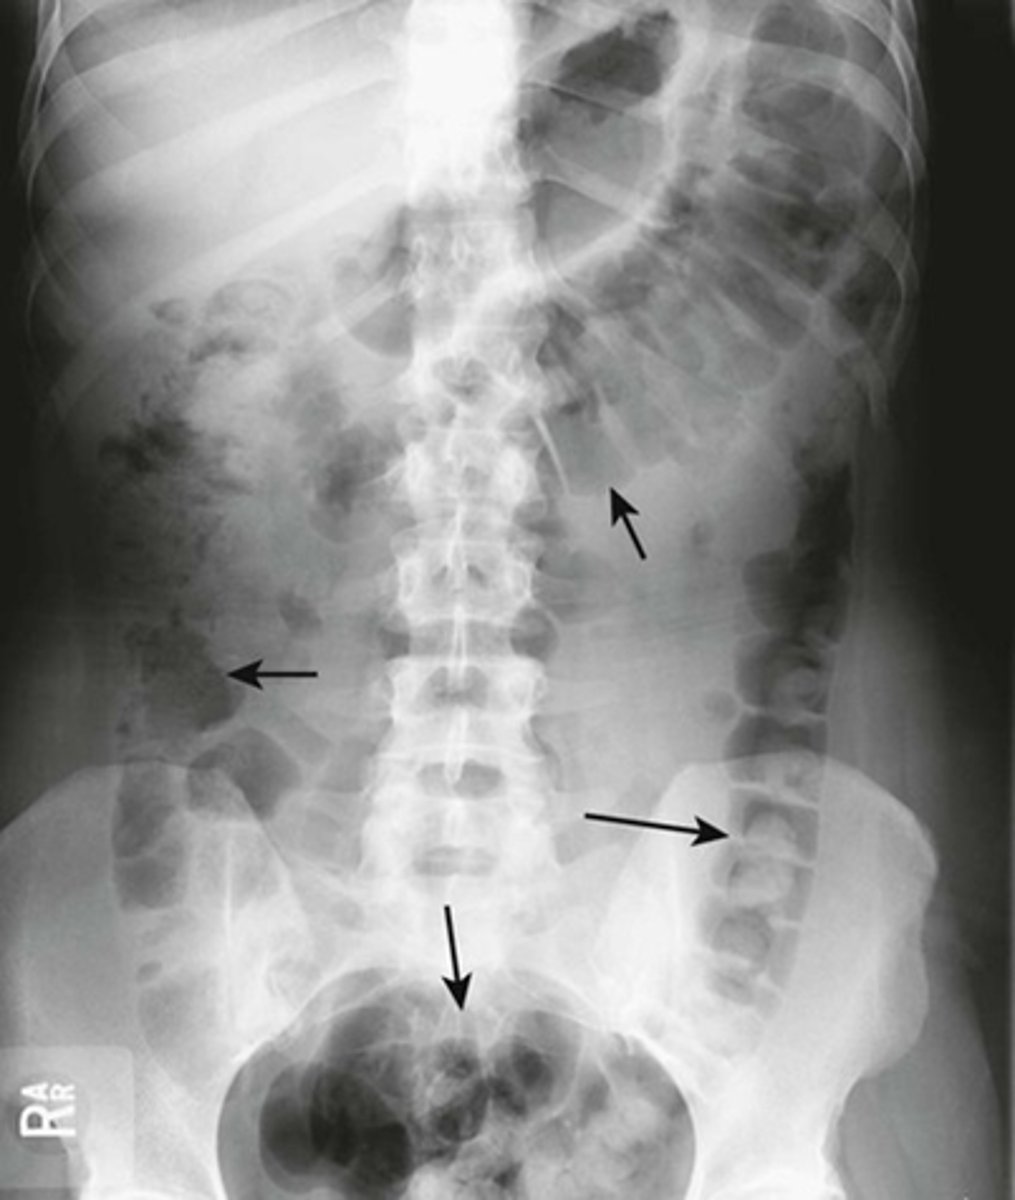

HEPATOMEGALY

BLACK ARROWS: displacement of all bowel loops from RUQ to iliac crest and across the midline.

Hepatomegaly is usually indicated by displacement of all bowel loops from RUQ to the iliac crest and across the midline, as in this pt with cirrhosis.

Sometimes the liver can be so enlarged that it will be obvious even on conventional radiographs

SPLENOMEGALY

WHITE ARROWS: spleen

BLACK ARROW: 12th posterior rib

Spleen is usually about 12 cm in length and DOES NOT project below the 12th posterior rib.

Splenomegaly can also displace the stomach bubble toward or across the midline.